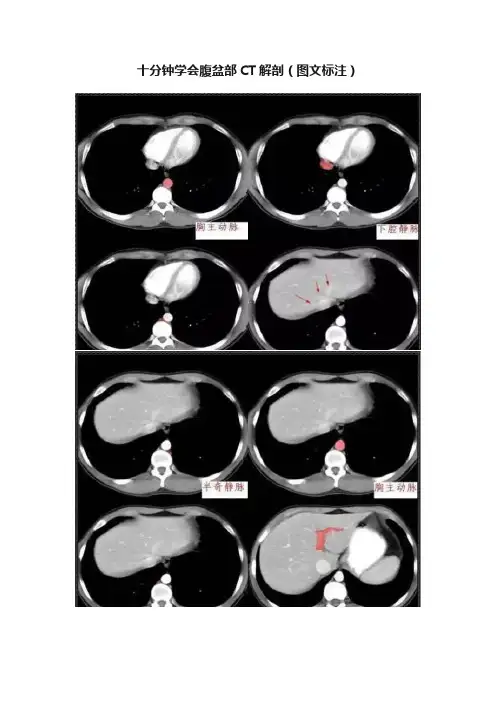

CT断层解剖图解颈胸腹 166第16断层1、右心室2、左心室3、胸主A4、下腔V5、肝右叶167第17断层1、右心室2、左心室3、胸主A 4、食管5、下腔V6、肝右叶168第18断层1、右心室2、左心室3、食管4、胸主A5、下腔V6、肝右叶 169第19断层1、右心室2、左心室3、胃底4、胸主A5、食管6、下腔V7、肝右V8、肝中V9 、左叶间V170第20断层1、食管2、胃底3、左肺下叶4、胸主A5、下腔V6、肝右叶171第1断层,经左 、右膈穹1、膈2、肝左外叶3、食管4、下腔V5、肝右叶176第6断层,经肝门V左支矢状部1、下腔V2、肝中 V3、肝门V左内支4、肝门V左支矢状部5、肝门V左外下支177第7断层,经肝门V左支横部1、胃体2、横结肠及其 脾曲3、肝尾状叶4、下腔V5、肝门V右前上支6、肝中V7、肝门V左支横部8、肝圆韧带裂9、肝门V左外下 支178第8断层,经肝门1、胃体2、横结肠及其脾曲3、空肠4、胰尾5、脾A6、乳头突7、弓状切迹8、 尾状突9、下腔V10、肝右后下V11、肝门V右后上支12、肝门V右前支13、肝门V右支14、肝中V15、 肝门V分叉处16、肝圆韧带179第9断层,经肝门V后支1、胃幽门部2、横结肠3、空肠4、降结肠5、胰体6 、左肾上腺7、右肾上腺8、肝右后下V9、肝门V右后支10、胆囊11、肝总管12、肝门V13、肝固有A1 4、脾A、V180第10断层,经胃幽门1、胃幽门部2、左肾3、左肾上腺4、脾A、V5、右肾上腺6、肝右后下V 7、胃幽门8、十二指肠上部9、肝门右切迹10、胆囊11、肝圆韧带181第11断层,经腹腔干1、横结肠2 、降结肠3、左肾4、胰体5、胰颈6、肝门V合成处7、腹腔干8、门腔淋巴结9、胆总管10、肝右后下V 11、肝门右切迹12、胆囊13、肝方叶小舌14、肝左外叶182第12断层,经主A孔裂孔1、横结肠2、空肠 3、降结肠4、左肾5、腹主A6、肠系膜上V7、胰颈8、胰头9、胆总管10、十二指肠降部11、下腔V 12、肝门V右后下支183第13断层,经肠系膜上A1、横结肠2、肠系膜上A3、肠系膜上A、V4、胰头5、胆总管6、 十二指肠降部7、右肾8、肝右叶9、胆囊底184第14断层,经十二指肠空肠曲1、肠系膜上A、V2、胰头3、胆总管4、胰钩 突5、十二指肠空肠曲6、左肾V7、腹主A8、下腔V9、肝右叶185第15断层,经十二指肠大乳头1、横结肠2、肠系膜上 A、V3、胰钩突4、十二指肠升部5、左肾A、V6、左肾V7、十二指肠大乳头8、胰头9、升结肠186第1 6断层,经左、右肾V1、胰头2、胰钩突3、空肠4、左肾5、左肾V6、十二指肠水平部7、腹主A8、右肾A 9、十二指肠降部10、右肾V11、升结肠12、肝右叶272第22断层,经肛管下方1、阴茎2、睾丸3、股薄肌 4、尿道球5、长收肌6、缝匠肌273第1断层1、腰大肌2、右髂总V3、右髂总A4、左髂总V5、左 髂总A6、L5椎体7、髂骨8、竖脊肌274第2断层1、右髂总V2、右髂总A3、左髂总V4、左髂总A 5、S1椎体6、髂肌7、臀中肌8、骶后正中嵴275第3断层1、右髂总A、V2、左髂总A、V3、骶管276第 4断层1、右髂总A、V2、左髂总A、V3、骶前孔4、臀中肌5、臀大肌277第5断层1、骶髂关节2、S1椎体3 、髂骨体4、骶后正中嵴365第11断层1、膀胱2、子宫颈3、肛管4、坐骨直肠窝5、闭孔内肌6、股骨头3 66第12断层1、膀胱2、子宫颈3、肛管4、闭孔内肌5、坐骨6、大转子367第13断层1、耻骨联合2 、尿道3、阴道4、肛管5、坐骨结节6、股骨颈368第14断层1、耻骨联合2、阴道3、肛管4、坐骨结节 5、闭孔外肌369第15断层1、耻骨下支2、阴道3、闭孔外肌4、大转子380第1断层,经C3/4椎间盘1、口咽部 2、左颈总A分叉处3、面V4、左颈内V5、颈长肌6、C3/4椎间盘7、脊髓8、椎A9、脊N节10、硬 脊膜11、头半棘肌12、头夹肌和颈夹肌13、斜方肌14、颈半棘肌15、最长肌16、肩胛提肌17、胸锁乳 突肌18、右颈内V19、前、中斜角肌20、头长肌21、颈交感干22、迷走N381第2断层,经C4椎体1、会 厌2、甲状软骨上角3、颈深淋巴结4、左颈总A5、头长肌6、椎A、V7、C4椎体8、脊髓9、硬脊膜 10、最长肌11、肩胛提肌12、头夹肌和颈夹肌13、颈半棘肌14、C4棘突15、椎弓板16、头半棘肌 17、斜方肌18、胸锁乳突肌19、右颈内V20、前、中斜角肌21、后结节22、椎内V丛23、颈长肌24 、前结节382第3断层,经T8椎体1、肋头关节2、关节突关节3、竖脊肌4、斜方肌5、椎弓板6、黄韧带7、第 8肋8、椎内V丛9、硬脊膜10、T8椎体11、右肺下叶12、右心房13、左心房14、左心室15、奇V 16、食管17、胸主A18、左肺下叶383第4断层,经L3椎体上份1、下腔V2、腹主A3、L3椎体4、透 明软骨终板5、腰大肌6、第2腰N7、马尾8、L3上关节突9、关节突关节10、L2棘突11、竖脊肌12、 腰方肌13、L2下关节突14、椎内V丛15、黄韧带16、十二指肠384第5断层,经L3/4椎间盘1、L3/4椎间盘 2、硬脊膜3、第3腰N4、黄韧带5、马尾6、L3棘突7、L3下关节突8、椎内V丛385第6断层,经L4椎体 1、L4椎体2、椎内V丛3、硬脊膜4、马尾5、腰丛6、第4腰N7、L4横突8、L4上关节突9、黄韧带10、棘间韧带11、竖脊肌12、腰方肌13、腰大肌386第7断层,经L4/5椎间盘1、右髂总V2、右髂总A3、左髂总V4、左髂总A5、乙状结肠A6、L4/5椎间盘7、腰丛8、关节突关节9、髂嵴10、竖脊肌